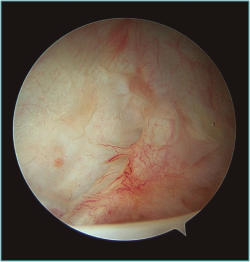

Al realizar la anamnesis, prestamos especial atención a estos síntomas ya que estos episodios repetidos de subluxaciones o microinestabilidad pueden conllevar a lesiones muy complejas e irreparables de la cápsula o, sobre todo, en el cartílago glenoideo (Figura 2).

Figura 2. Visión desde portal posterior del hombro derecho. Se observa una lesión intrasustancia de la cápsula anterior.